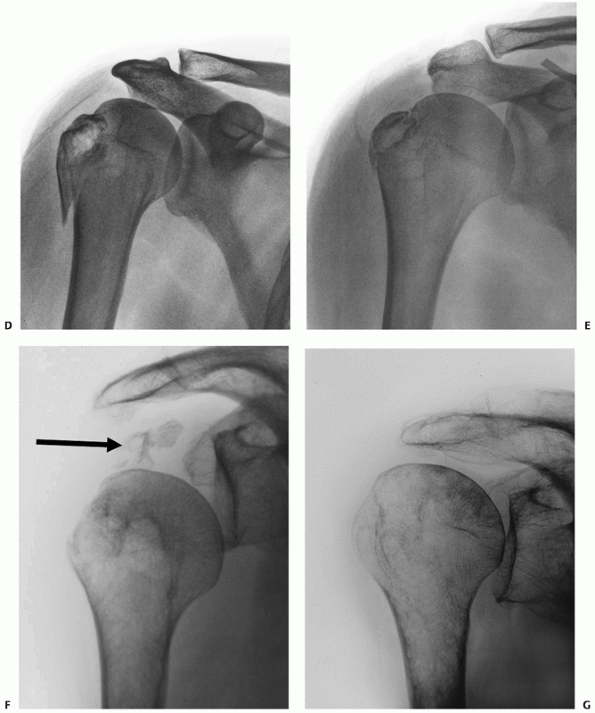

![]() |

FIGURE 35-9 A,B.

Undisplaced and stable fracture configurations are best treated nonoperatively in most elderly patients, as shown in these two examples. |

FIGURE 35-10 Many seemingly isolated greater tuberosity fractures (A) actually have undisplaced anatomic neck fracture lines (arrow), which are only seen when a correctly orientated anteroposterior view is taken (B).

FIGURE 35-11 An undisplaced greater tuberosity fracture may not be visible on conventional radiography (A) and may only be seen on magnetic resonance imaging (B,C). (continues)

FIGURE 35-11 (continued) Greater tuberosity fractures vary widely in their size, ranging from larger fragments (D) to smaller avulsion-type injuries (E).

These may displace in the same manner as a rotator cuff tear, with retraction of the tendon leading to progressive displacement of the bone fragment (arrow) (F). Untreated, this may lead to a rotator cuff-deficient shoulder with a high-riding humeral head and rotator cuff arthropathy (G). |